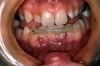

OAC is

acute

just happened, immediate post extraction - can see bleeding, potential prolapse of lining of maxillary antrum

OAF is

chronic

communication made - management failed and opening persists - sinus tract has been created now

no bleeding